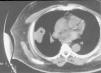

Varón de 63 años con hemoptisis, dolor pleurítico y masa pulmonar

A 63-year-old male with hemoptysis, pleuritic pain, and lung mass